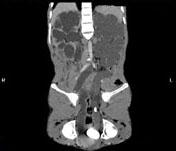

问题 男,33岁,反复尿频,尿急,尿痛3年余,排尿困难4个月,尿常规:蛋白(+),红细胞01/HP,白细胞(++),CT扫描图,下列诊断哪项说法正确 ( )

选项 A、双侧肾积水,双侧输尿管扩张 B、膀胱多发性假性憩室 C、膀胱慢性炎性肉芽肿 D、膀胱癌 E、膀胱结石

答案 ABCE